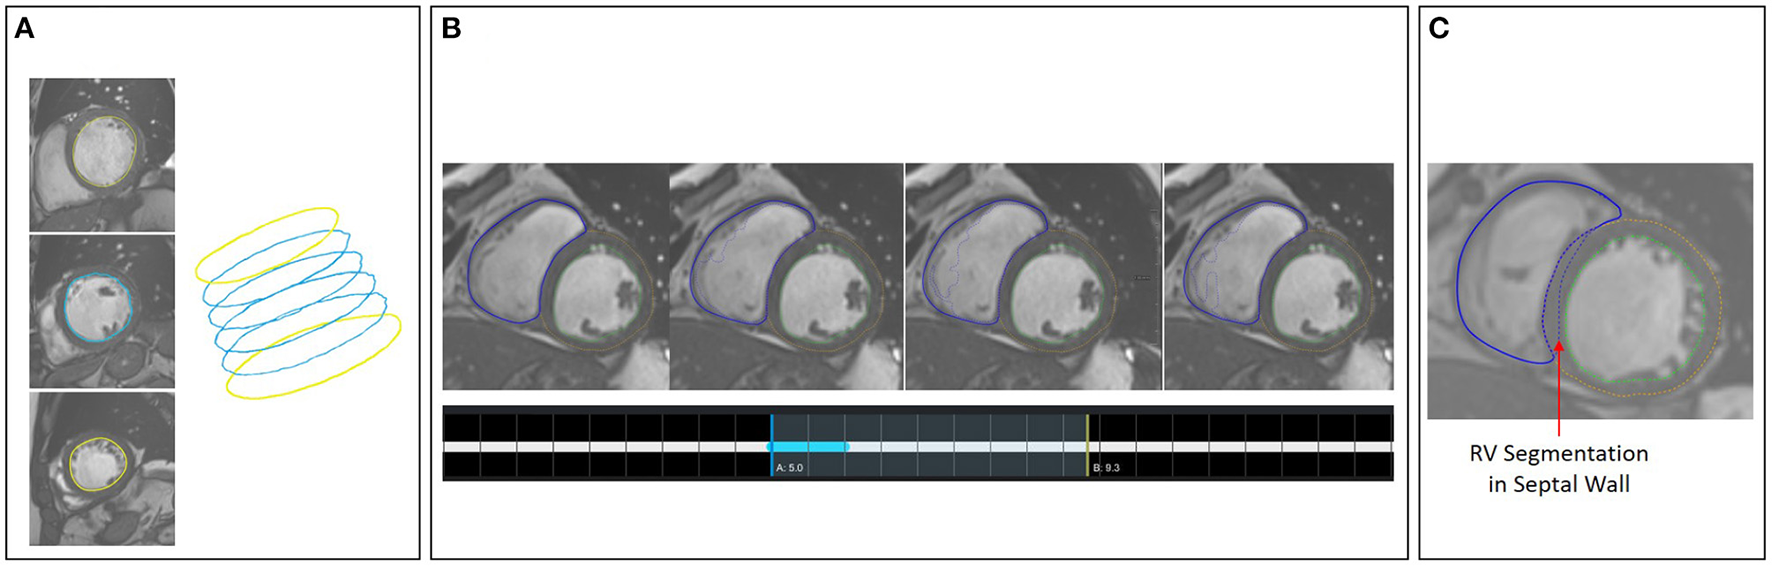

Figure 6

(A) Shape-based interpolation: manual contours (yellow) are defined on two slices. The blue contours represent the interpolated results. (B) Temporal correction: top row shows a series of time frames of a cine MRI dataset. The solid contour shows the manually corrected contours. The dotted contours represent the incorrect segmentation results. The time-point widgets show the range the user selected for correction via contour propagation. (C) Correction with logical conditions: the contour of the right endocardium was originally drawn into the septal wall (blue dotted contour). The solid contour represents the corrected segmentation.